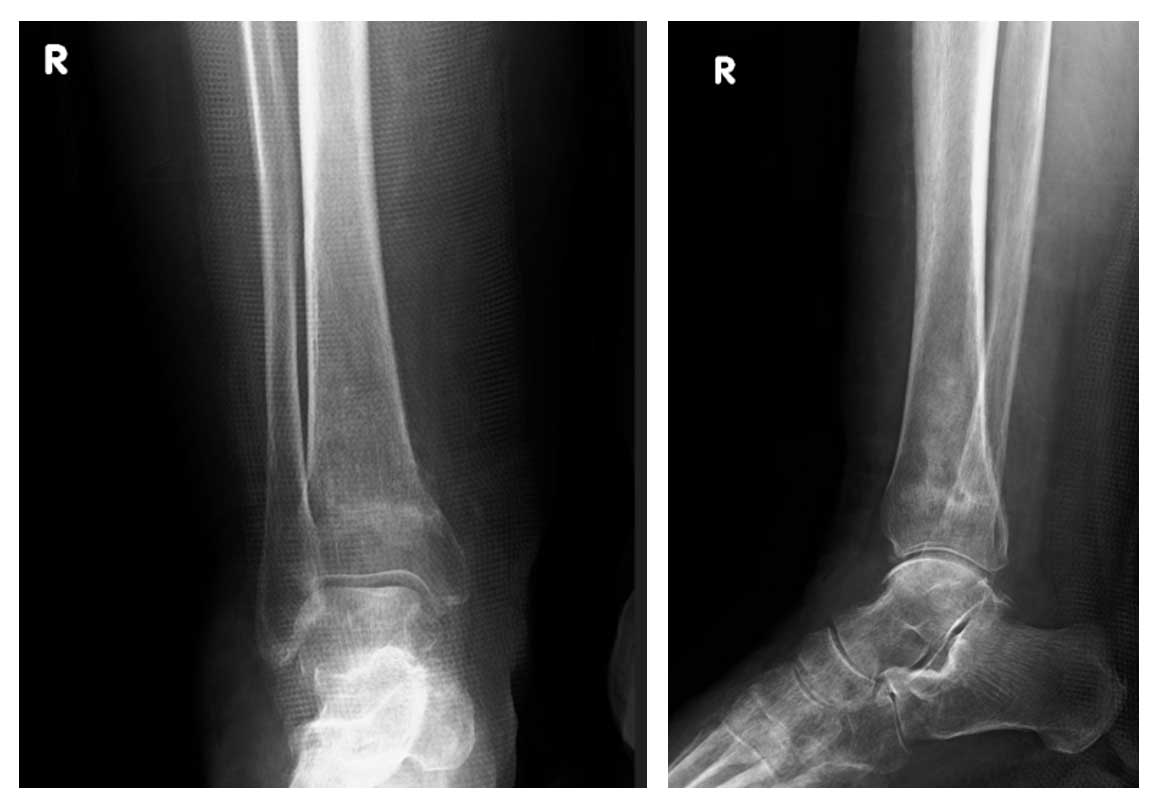

Kadın hasta, ayak bileği çevresinde ağrı ve şişlik şikayetleriyle başvurdu. Yapılan radyolojik tetkikler ve biyopsi sonucunda distal tibia yerleşimli osteosarkom tanısı konuldu. Taramalarında metastaz saptanmadı ve cerrahi tedavi planlandı.

Ameliyat Öncesi: Röntgende distal tibiada düzensizlik görülmekte.